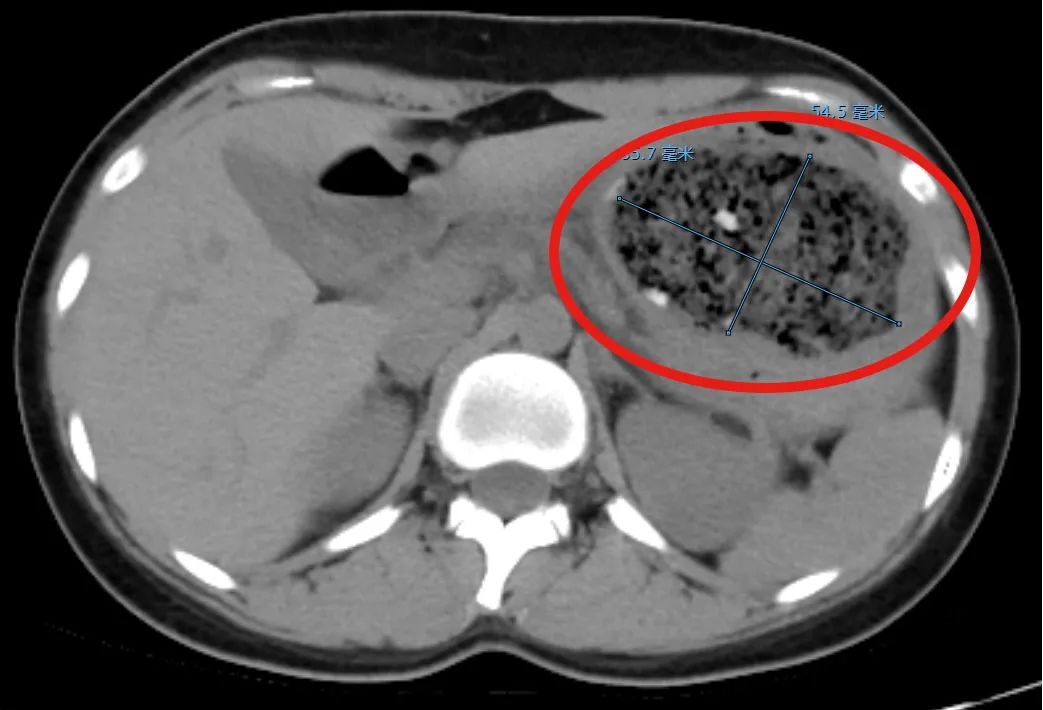

接受咨询的消化内科副主任杨晶在简单询问病史后,为倩倩安排了一次腹部CT扫描检查,发现一次8.6。cm×大约5.5厘米的巨大异物把她的胃塞得满满的!

经过进一步的胃镜检查,杨晶发现倩倩胃内的结石体积很大,几乎没有留下任何间隙,这使得常规的异物圈套器无法施展。